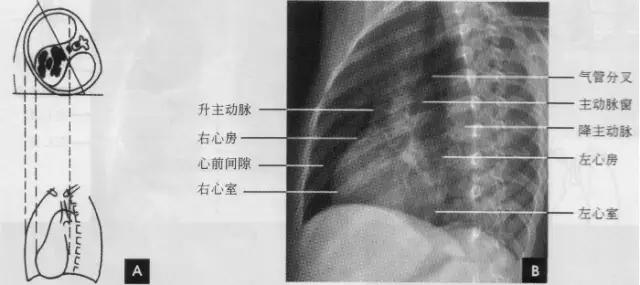

(三)左前斜位 从后前位向右旋转约60。得到左前斜位(又称第二斜位).此时室间隔与中心x线接*平近**行。因此.两个心室大致是对称的分为两半,前方一半为右心室.后方一半为左心室。心前缘上段为右心房.下段为右心室,右心房段主要由右心耳构成,房室分界不清。右心房影以上为升主动脉,两者相交成钝角:心后缘可分为上下两段,上段由左心房,下段则由左心室构成。左心室段的弧度较左心房大,两个不同弧度的交接点,可作为两者的分界。通过主动脉窗可兄气管分叉,主支气管和肺动脉,左主支气管下方为左心房影。左前斜位可了解各房室和主动脉情况(如下图)。

(四)左侧位 心影从后上向前下倾斜,心前缘下段为右心室前壁,上段则由右心室漏斗部与肺动脉主干构成,再苣上为升主动脉前壁,直向上走行。这些结构与翦髓壁之间的三角形透亮区称为胸骨后区。心后缘上中段由左心房构成,下段则由左心室构成。心后下缘、食管与膈之间的三角形间隙,为心后食管前间隙(如下图)。